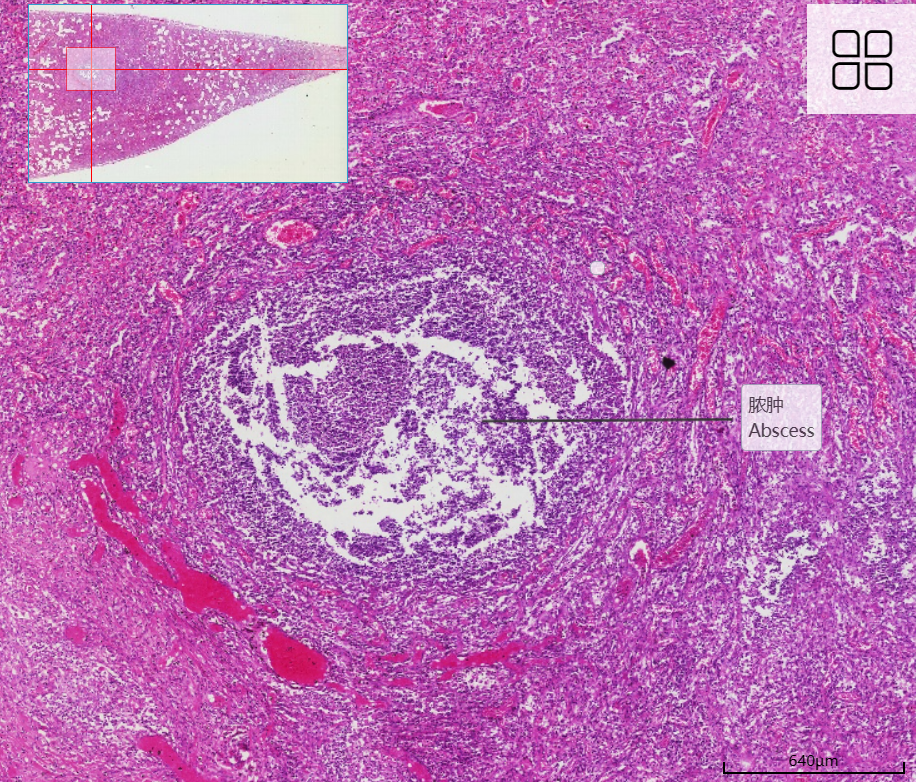

2 肺脓肿